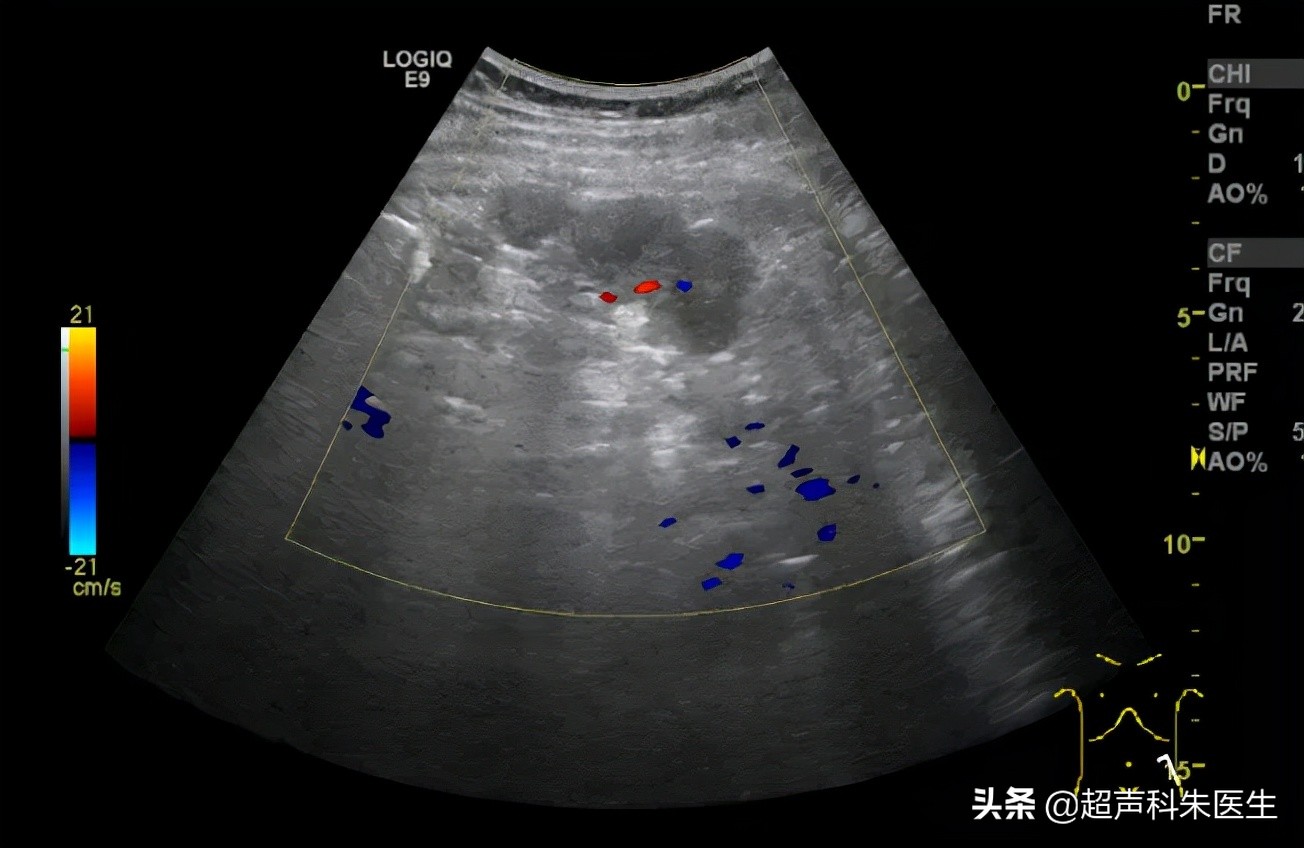

盆腔可见无回声区团块,大小约 15.1cm×11.2cm ,界尚清,内透声差,可见细密点状回声,腔内可见高回声突起,大小约 5.9cm×3.2cm ,高回声突起回声不均,可见少许血流信号;无回声团块左侧壁连续性中断,可见高回声结节向外凸出,大小约 7.2cm×3.2cm ,界尚清,内回声不均,内可见高/强回声斑,可见少许血流信号,探及动脉型血流频谱, RI 0.66 。

盆腔无回声包块上方(左侧髂血管旁、网膜)可见数个低/混合回声结节,大者大小约 2.8cm×2.8cm ,界尚清,内回声不均,可见少许血流信号(见图 1-4 )。

图 4 肠管/网膜上低回声结节